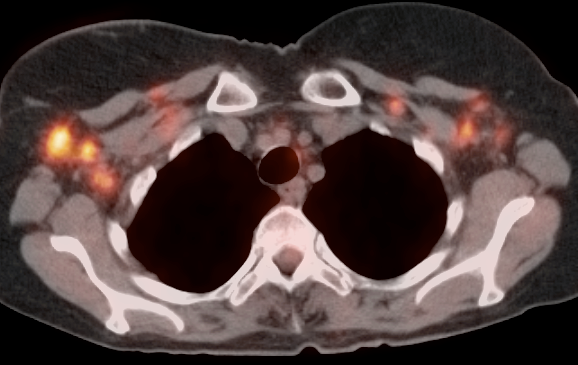

Metastatic Disease:

• Direct invasion of adjacent structures.

• Lymphatic spread to pelvic and retroperitoneal lymph nodes.

• Hematogenous spread, often to lungs, liver, and bone.

False Negatives:

• Nodes or metastatic deposits < 8.0 mm